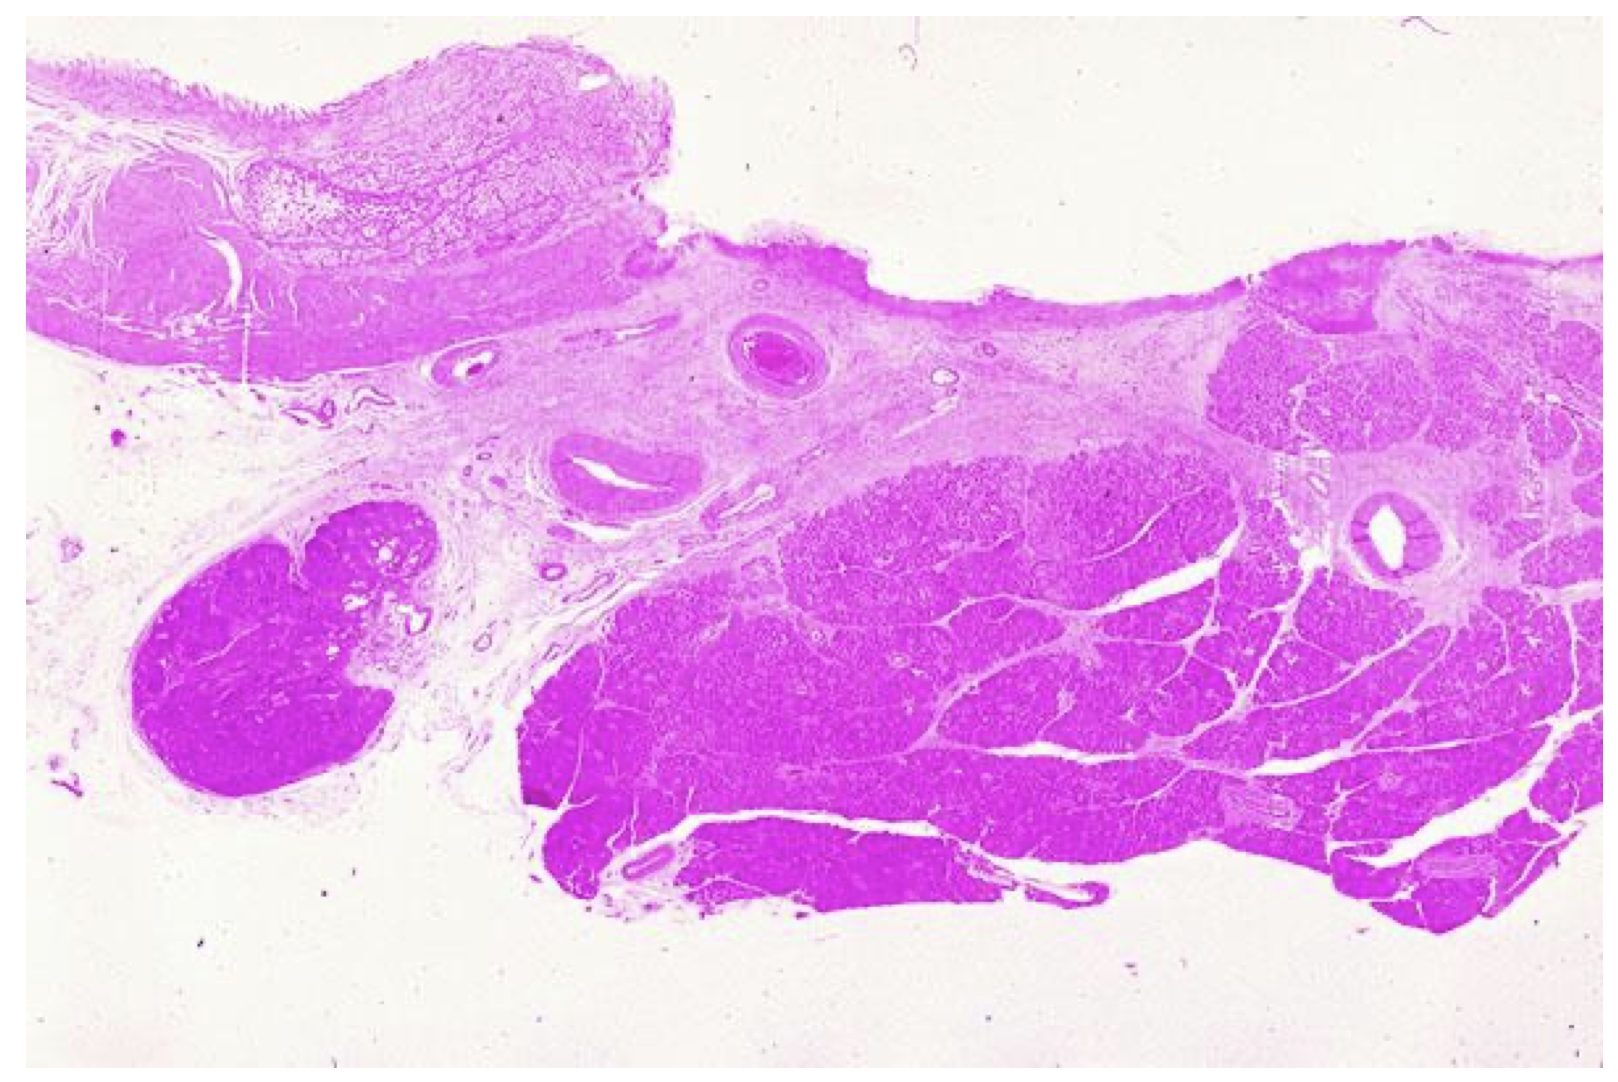

Duodenal ulcers, H/E microscopic slide, overview

normal epithelium on the left, which leads to a large ulcer. The ulcer can be seen to erode into the underlying pancreas. At the base of the ulcer, one would find RBCs, fibrin, and granulation tissue. A higher power view is available.